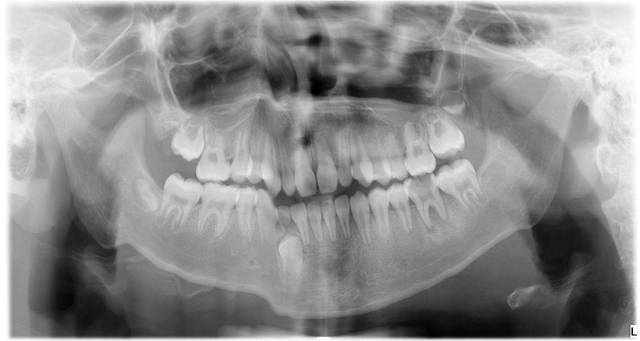

儿童慎拍牙片,儿童牙片图片

儿童牙片图片

儿童全景牙片图片

儿童牙片全景

儿童牙齿x光片

儿童牙齿全景片

儿童牙片怎么看图解

牙片图片